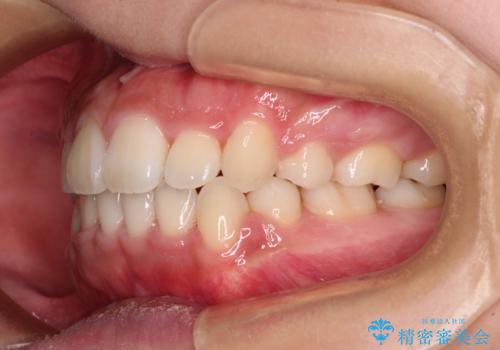

- 前歯のデコボコと口元の突出感を気にして来院された患者様です。

上下左右第一小臼歯4本を抜歯し、ワイヤー装置にて口元を引っ込めるよう矯正治療を行うこととしました。

非常にスムーズに歯列移動が行われ、当初は2-2.5年を予想していましたが、僅か1年4ヶ月で治療を終えることができました。